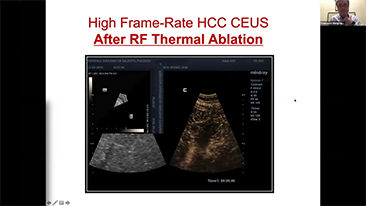

Comment voir le foie au mieux??

L'imagerie de contraste joue un r?le important en cas de lĂŠsions hĂŠpatiques focales, par exemple hĂŠmangiome ou cancer hĂŠpatique. La technologie d'imagerie de contraste UWN+ ultra-large et non linĂŠaire offre une meilleure pĂŠnĂŠtration, un rapport contraste-tissu plus ĂŠlevĂŠ, avec un index mĂŠcanique (IM) plus faible et une observation plus longue du temps de perfusion.